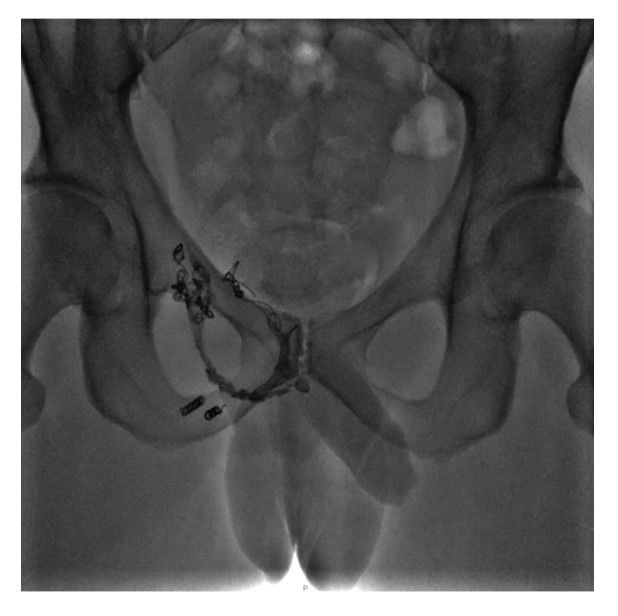

После заполнения мертвого пространства микрокатетера «progreat» ДМСО вводили эмболизат со скоростью около 0,16 мл/мин с непрерывным флюороскопическим контролем, при этом пациент выполнял затяжной маневр Вальсальвы. Во время введения эмболизата пациент отметил покалывание и легкое жжение в промежности и правой ягодичной области, прекратившиеся сразу после завершения введения. При контрольной флебографии виден полный стаз контрастированной крови, определяются рентгенконтрастные массы полимера «КАП» в правой части параспростатического венозного сплетения (рис. 11). После окончания процедуры эмболизации инструментарий и интродьюсер, находящийся в v. basilica, извлекали. В завершение всей процедуры на место пункции накладывали асептическую давящую повязку.

Рис. 11. Рентгенограмма тазовой области сразу после завершения процедуры эмболизации.